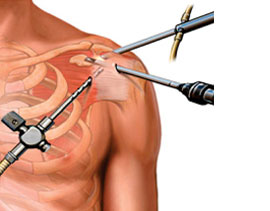

Shoulder Arthroscopy

Shoulder Arthroscopy has been performed since the 1970s. It has made diagnosis, treatment, and recovery from surgery easier and faster than was once thought impossible.